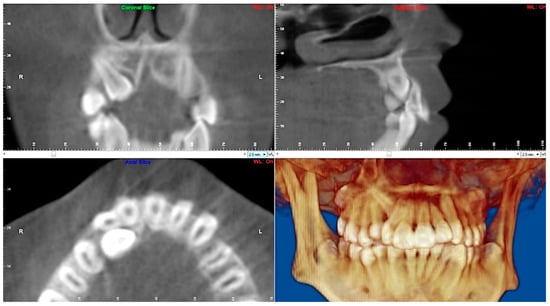

- Evaluation of buccal and lingual cortical plates: Figure 5, Figure 6 and Figure 7 show a case in which the mandibular lateral incisors are positioned lingual to the central incisors. Both mandibular lateral incisors are adjacent to each other. Figure 5 shows and intraoral occlusal photos with retained deciduous mandibular lateral incisors. There was no way to evaluate the buccal and lingual cortical plates through conventional 2D panoramic, periapical or occlusal radiographs. Therefore, CBCT was acquired and collimated to the area of teeth in order to assess the relationship of the four mandibular incisors to the labial and lingual cortical plates as well as to the adjacent teeth. As Figure 6 and Figure 7 display, CBCT shows that all permanent mandibular incisors are sound. It is important to note that thin buccal and lingual cortical plates may not be seen via CBCT—this does not denote that they are not present. In other words, CBCT images may not show a clinically present thin buccal and lingual cortical plates. In this case, the diagnostic information obtained from CBCT is far more significant than the information obtained from any other radiographic imaging technique.